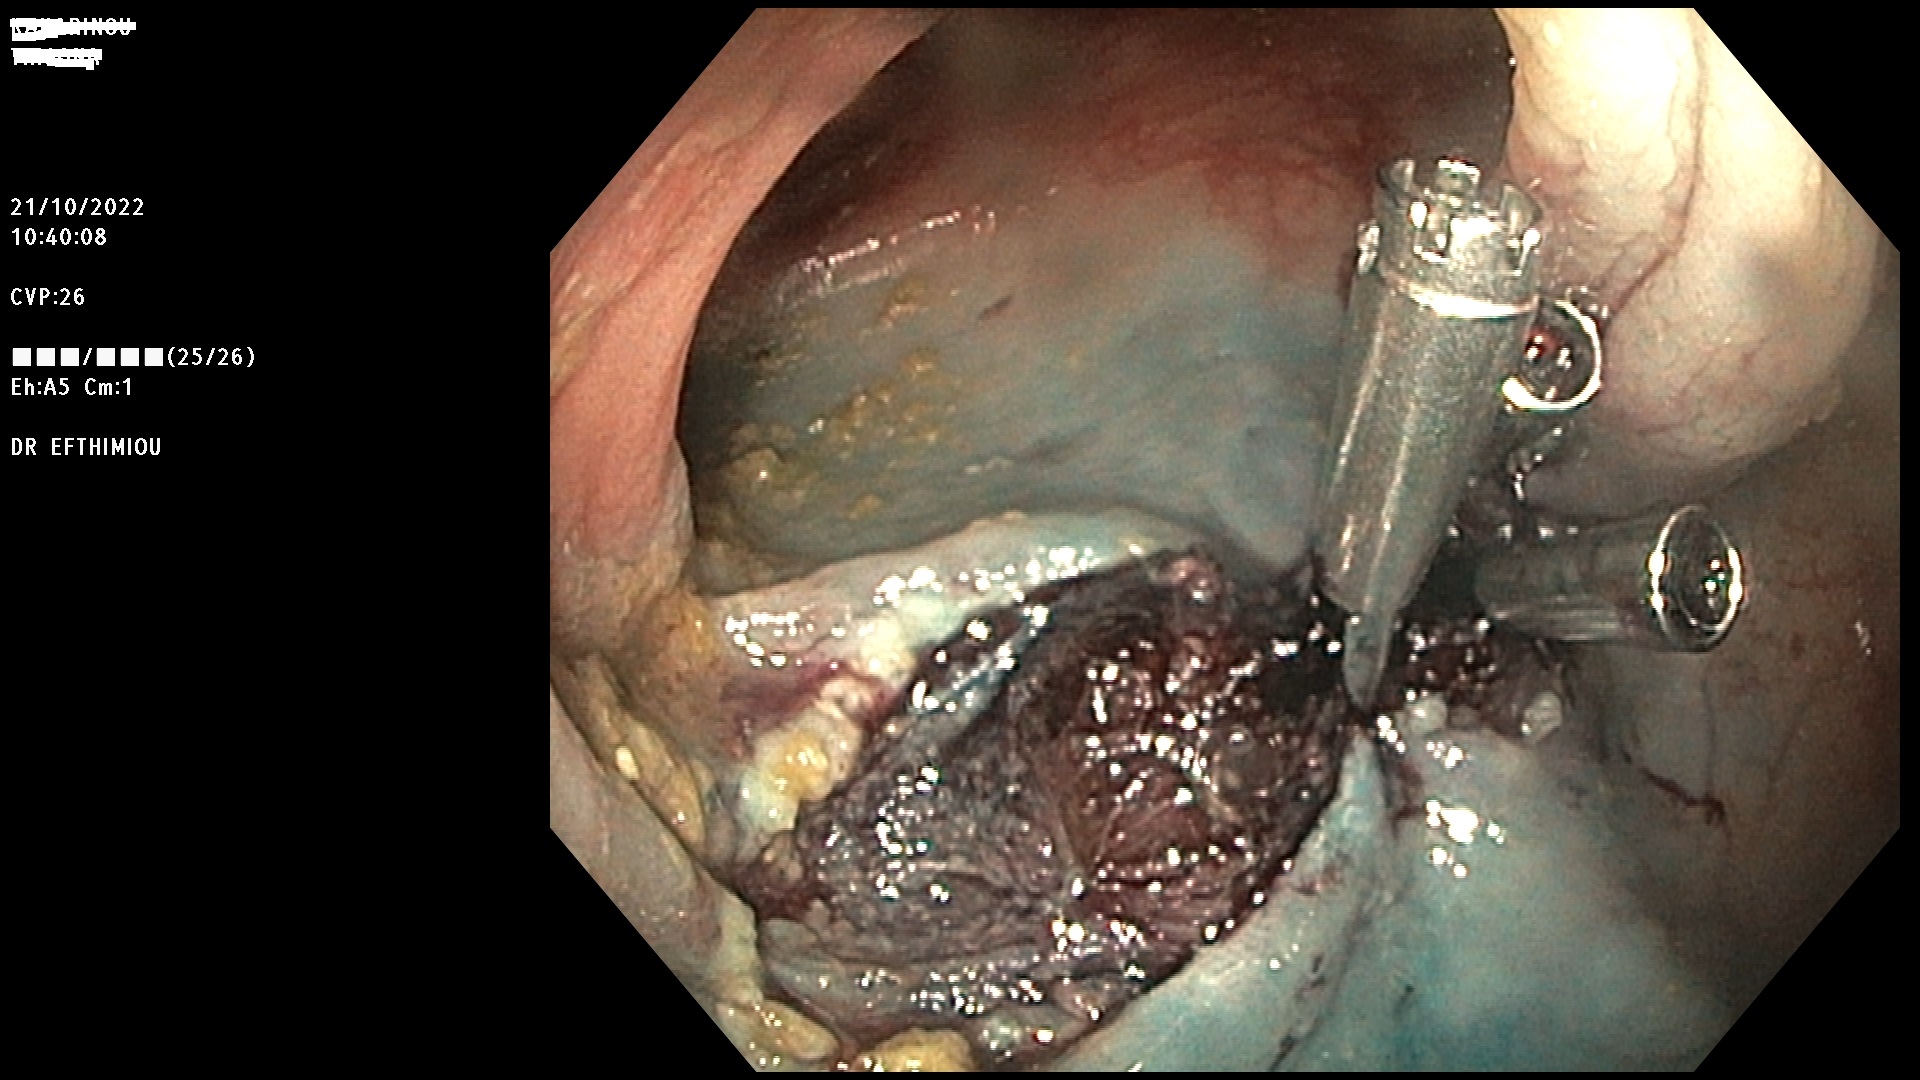

Η επέμβαση γίνεται κατά τη διάρκεια της κολονοσκόπησης με τη χρήση

διαφόρων εργαλείων (λαβίδες, βελόνες υποβλεννογόνιας έγχυσης, βρόχοι

διαθερμίας, ψυχροί βρόχοι, endoloops, κ.ά.) ανάλογα με το μέγεθος, τη

μορφολογία και την εντόπιση του πολύποδα (Εικόνες 1-3). Ο ασθενής

βρίσκεται σε ήπια καταστολή («μέθη») και δεν αισθάνεται καθόλου πόνο.